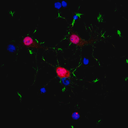

ANTICUERPO ANTI-NEUN, HUESPED CONEJO. 100 µg